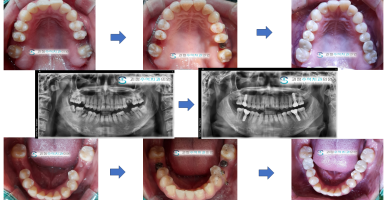

교정병행 다수의 임플란트

벌어진 앞니를 교정장치를 사용하여 모아주고 다수의 임플란트를 진행한 사례입니다.